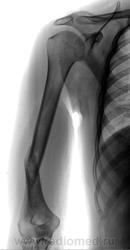

Пол пациента: Мужской пол Тип патологии: Травма Область исследования: Скелетно-мышечная система Методы исследования: Rg Сняли ГИПС, консолидацию ищут... https://radiomed.ru/sites/default/files/styles/case_slider_image/public/user/12/2.201406170044.jpg?itok=gshoRdle ID:39070 Чт, 19/06/2014 - 14:54 #1 Сергей Кузьминов Не на сайте Был на сайте: 1 год 6 месяцев назад Зарегистрирован: 06.10.2012 - 15:51 Публикации: 11813 Здесь её нет.Вторая проекция обязательна. Пт, 20/06/2014 - 10:00 #2 Катенёв Валенти... Не на сайте Был на сайте: 7 лет 6 месяцев назад Зарегистрирован: 22.03.2008 - 22:15 Публикации: 54876 Сергей Кузьминов wrote: Здесь её нет.Вторая проекция обязательна. Вы правы.Приложения: Пт, 20/06/2014 - 14:24 #3 Сергей Кузьминов Не на сайте Был на сайте: 1 год 6 месяцев назад Зарегистрирован: 06.10.2012 - 15:51 Публикации: 11813 Савсем нет консолидации.Давно ли сломано? Пт, 20/06/2014 - 21:06 #4 svetlana292929 Не на сайте Был на сайте: 4 года 1 месяц назад Зарегистрирован: 18.06.2012 - 13:53 Публикации: 869 а угловое смещение не смущает никого? Пт, 27/06/2014 - 10:58 #5 Катенёв Валенти... Не на сайте Был на сайте: 7 лет 6 месяцев назад Зарегистрирован: 22.03.2008 - 22:15 Публикации: 54876 Сергей Кузьминов wrote: Савсем нет консолидации.Давно ли сломано? Сломано 3 месяца тому назад. Пт, 27/06/2014 - 15:05 #6 Сергей Кузьминов Не на сайте Был на сайте: 1 год 6 месяцев назад Зарегистрирован: 06.10.2012 - 15:51 Публикации: 11813 Печально.Наверное, надо было оперировать.

Здесь её нет.Вторая проекция обязательна.

Савсем нет консолидации.Давно ли сломано?

а угловое смещение не смущает никого?

Сломано 3 месяца тому назад.

Печально.Наверное, надо было оперировать.